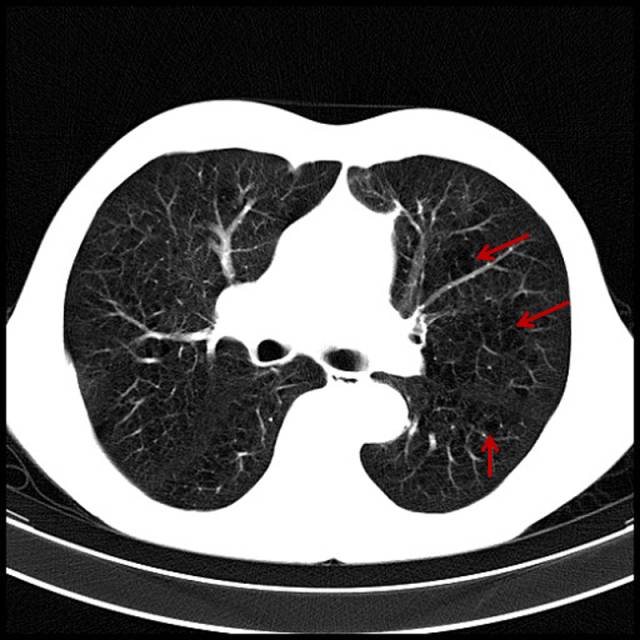

吸烟导致的重度肺气肿

男,72岁,吸烟史。

图片

图8

双肺布满小无肺纹区。这类患者气短已经相当明显,已经意识到与吸烟有关。只要一解释,一般都会立马戒烟。此类患者更多的是非常紧张,不断地询问:有什么好方法?能治好不?要知如今何必当初。其实年龄越大越紧张。